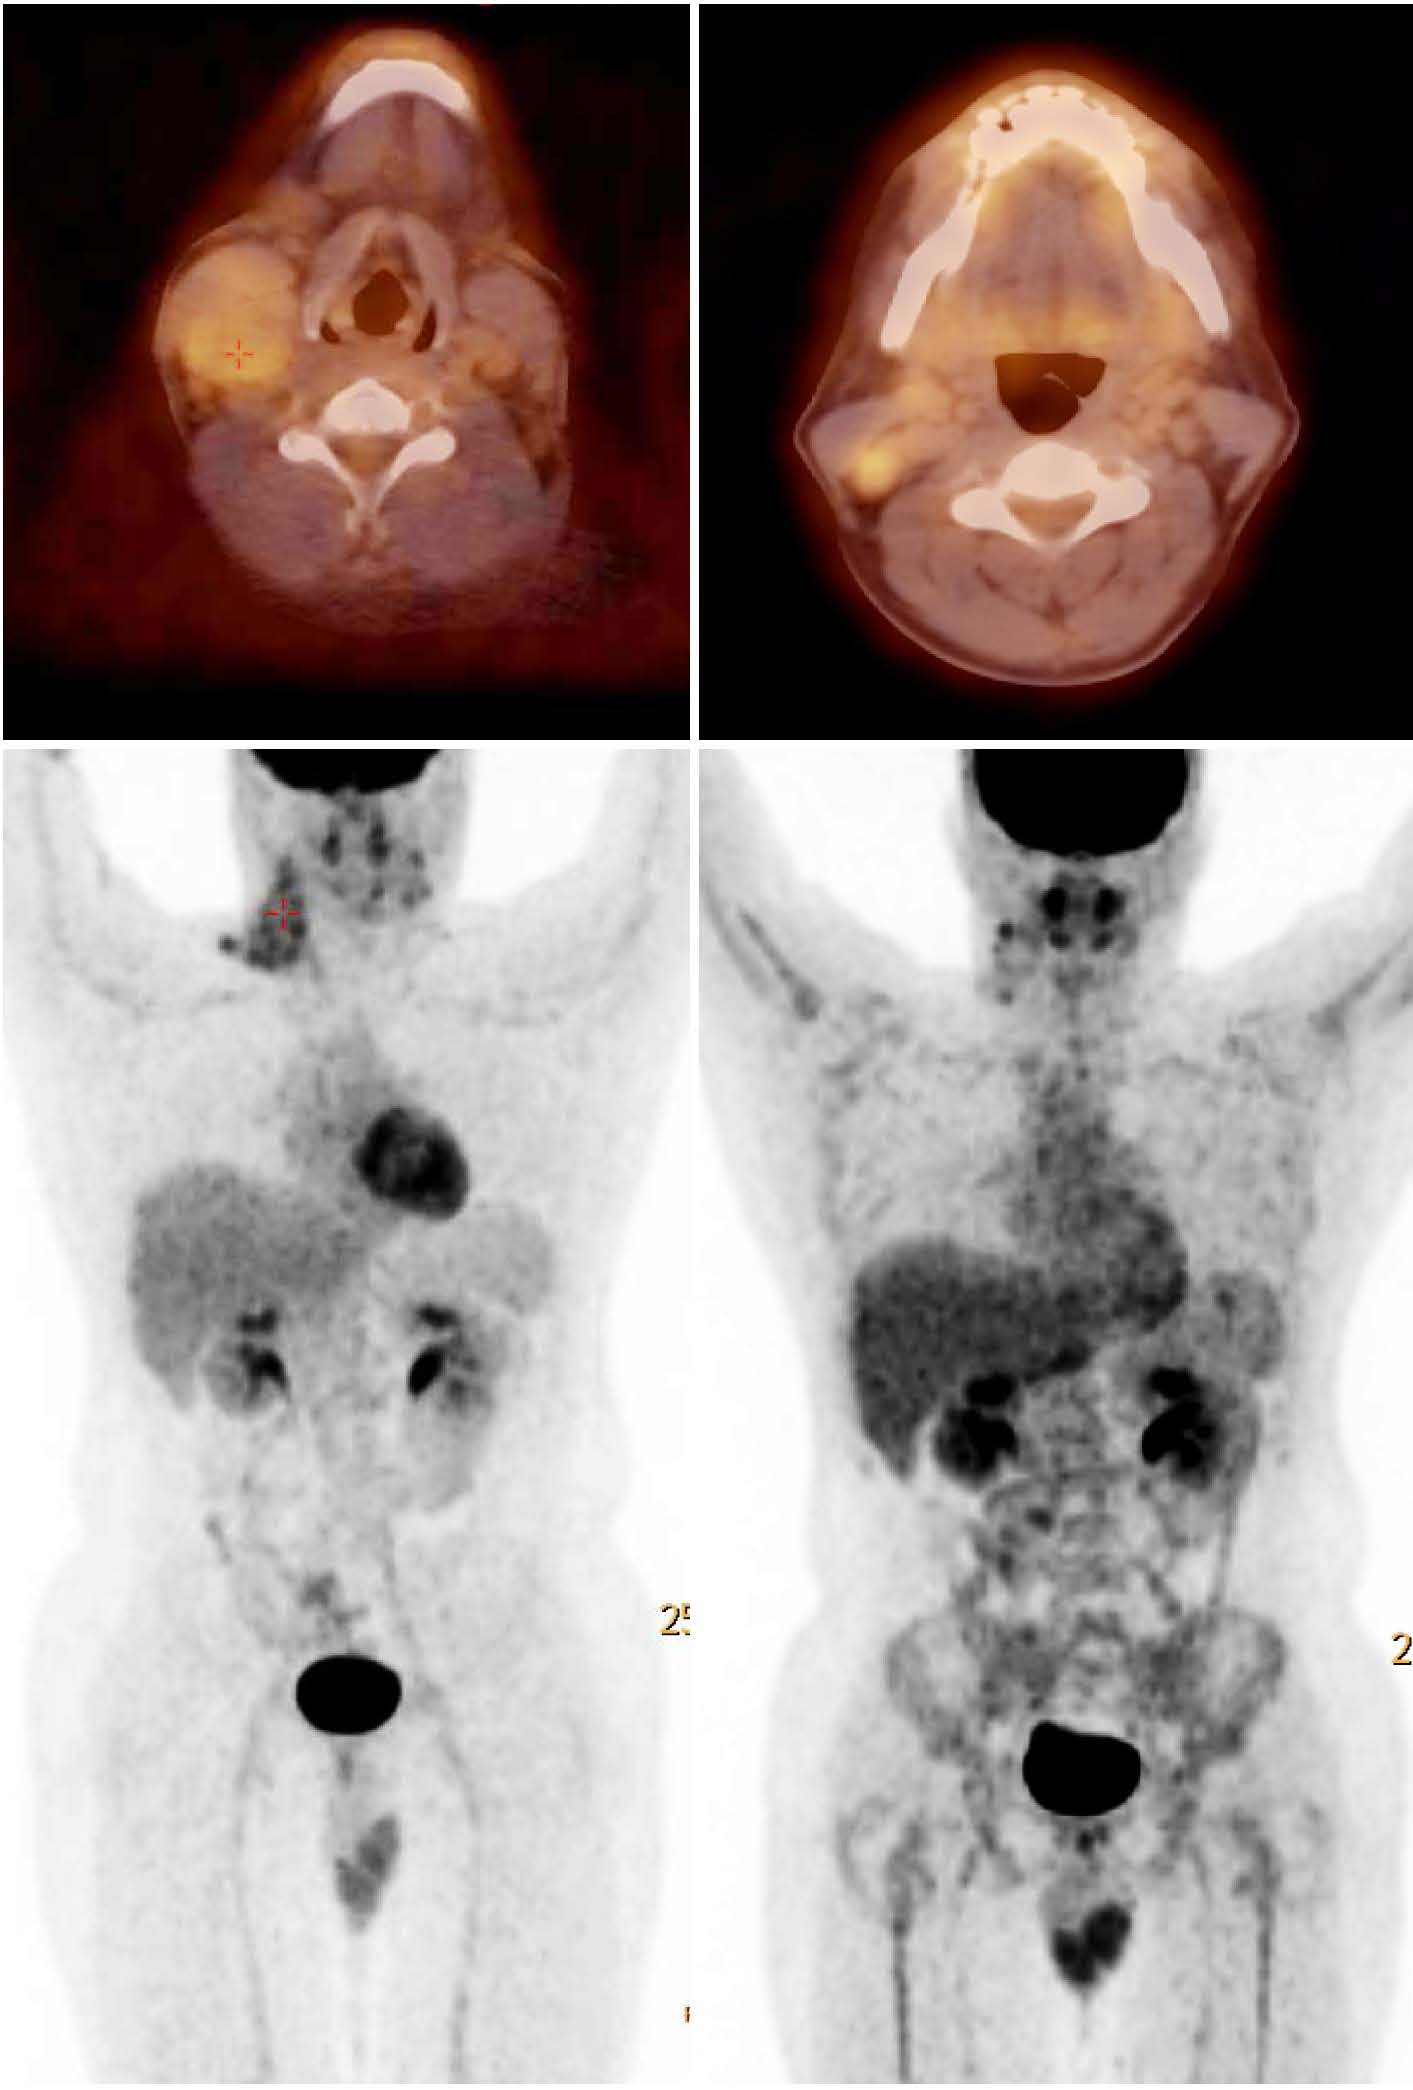

Диагностика лимфомы Ходжкина с помощью ПЭТ и КТ

Раздел: Светлые идеи